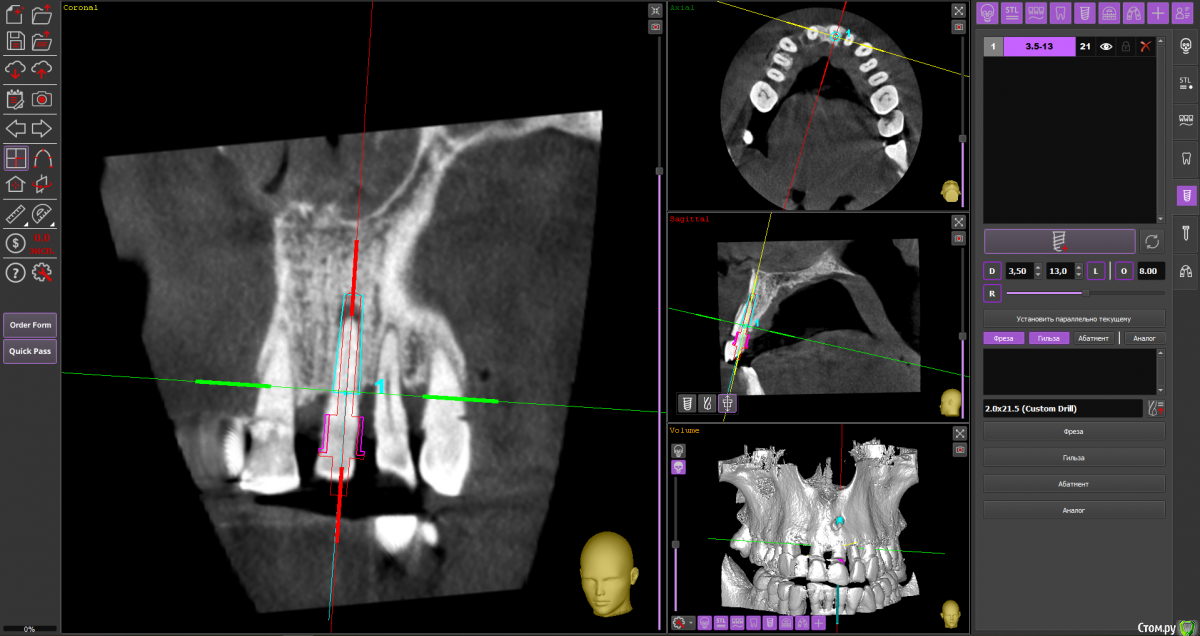

almaz7888 Опубликовано 28 января, 2021 Поделиться Опубликовано 28 января, 2021 Доброе утро коллеги! Планирую одномоментную имплантацию в область 2.1 зуба ( AnyRidge 3.5*11.5). В области апекса костный дефект. Думаю заполнить ксенографтом и перекрыть резорбируемой мембраной 1.5*2.0. Думал насчет спейсера Стоит ли такой имплант сразу нагрузить? или же лучше сделать адгезивный мост. Ссылка на комментарий

alboard Опубликовано 28 января, 2021 Поделиться Опубликовано 28 января, 2021 В том положении, которое на кт, сомневаюсь, что получите торк и сможете нагрузить... Взять подлиннее, поставить небнее и заглубить еще 4 Ссылка на комментарий

Irouil Опубликовано 28 января, 2021 Поделиться Опубликовано 28 января, 2021 Винт длиннее, выход в резцовый, стт, временная коронка 1 Ссылка на комментарий

almaz7888 Опубликовано 28 января, 2021 Автор Поделиться Опубликовано 28 января, 2021 Спасибо, тогда возьму 3.5*15. А резцовый нерв коагулирую и заполняю канал графтом или же можно без прижигания обойтись? Ссылка на комментарий

Irouil Опубликовано 28 января, 2021 Поделиться Опубликовано 28 января, 2021 Резцовый - это край, а не канал) Дальше либо цемент через индивидуальный абатмент, либо угловой абатмент и шаровидная отвёртка под винтовую 2 Ссылка на комментарий